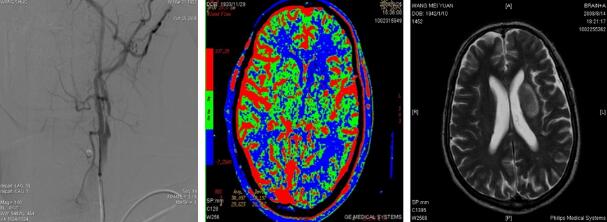

2.脑血管病及脑血管介入:在国内较早建立了卒中单元和脑血管介入诊疗组,建立多学科合作的卒中绿色通道, 24全天候急诊脑血管介入值班,开展了全脑血管造影术(DSA)、静脉溶栓、动脉溶栓术及动静脉联合溶栓术、大血管急性闭塞取栓及支架置入、颅内、外脑供血动脉狭窄球囊成形术、支架植入术、复杂高危脑动脉狭窄的血管内介入治疗术、颅内外脑动脉慢性闭塞的再通治疗等;诊治水平处于国家先进行列,年导管量约1500例次。